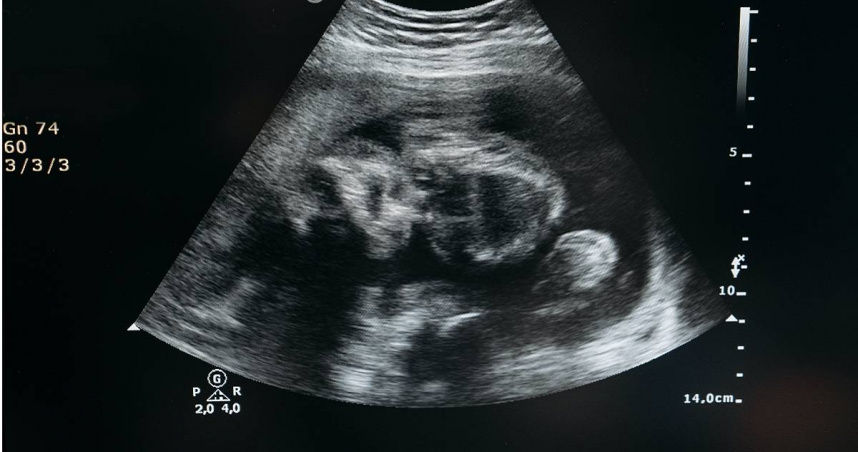

婦產科醫師李偉浩在節目《醫師好辣》表示,這名有長期私密處流血和肚子痛的女子前來就醫時,就安排超音波檢查,結果「一掃,懷孕了」,而且胎兒看起來已有20週、約5個月大左右,李偉浩醫師也立即跟女子道賀「恭喜,42歲還懷孕了」,怎知對方卻一臉錯愕與不敢置信。

▲一名裝有避孕器10年的女子,因肚子痛就醫後驚知已懷孕5個月。(示意圖/Pexels)